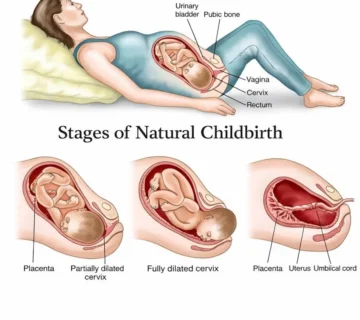

At this stage, the placenta is close to its maximum size, usually measuring 15–20 centimeters in diameter and 2–3 centimeters in thickness. Enlargement of the uterus and placenta may cause a sensation of heaviness, pelvic pressure, and swelling of the legs, which are common maternal symptoms at this time.

The lungs are nearly fully developed, although final maturation continues until birth. The umbilical cord, which provides the vital connection between the fetus and placenta, usually measures 30–90 centimeters, with an average length of 50–60 centimeters. It has a whitish, coiled appearance and is responsible for delivering oxygen and nutrients to the fetus.

Labor at week 38 of pregnancy is considered normal, and many babies are born at this time. However, the exact onset of labor cannot be predicted and may occur during this week or later. The body usually shows signs of readiness before labor begins.

Signs Labor May Be Approaching

-

Regular uterine contractions increasing in intensity and frequency

-

Pelvic pressure or the baby “dropping”

-

Increased vaginal discharge or passage of bloody mucus (bloody show)

-

Persistent lower back pain radiating to the thighs

-

Rupture of membranes (water breaking), sudden or gradual

One sign alone does not necessarily indicate labor, but a combination may suggest true labor.

Difference Between True Labor and False Labor

Many women experience Braxton Hicks contractions, which can be mistaken for labor.

True labor contractions:

-

Regular and progressive

-

Do not improve with rest or position changes

-

Increase in intensity over time

False labor contractions:

-

Irregular

-

Improve with rest or movement

-

Intensity remains stable